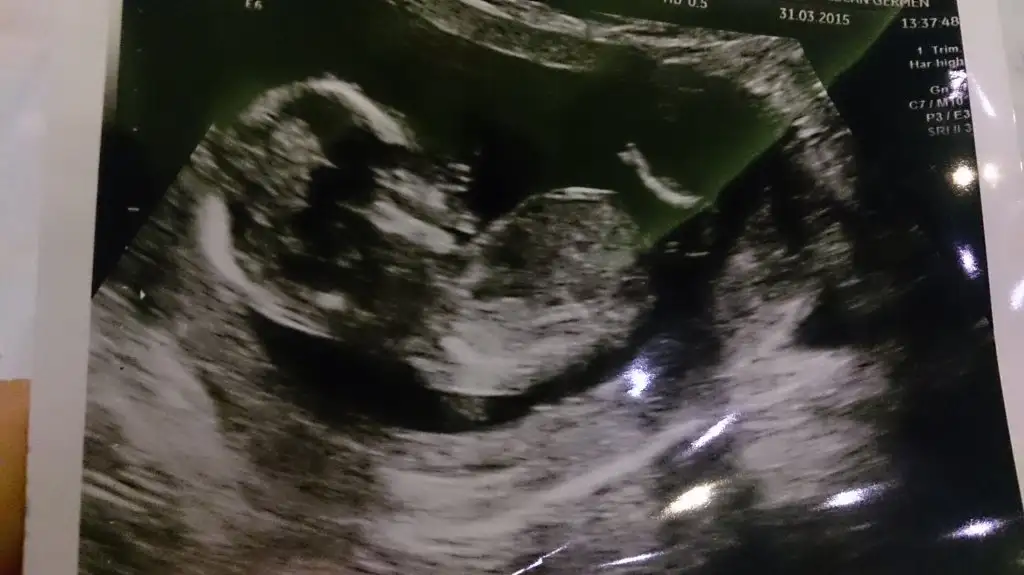

Canım zaten yinede erkek olabilir çünkü ben tam kıza benzetemedim açıkcası :)Canım doktorda baya dikkatli baktı o bacak mı diye. O da emin olamadı, net birşey diyemem dedi, kız gibi dedi. Saol canım yorum için.

Canım zaten yinede erkek olabilir çünkü ben tam kıza benzetemedim açıkcası :)

Kiz gibi canim cok net deil ama emin olamadim.. kac haftalik dokor bisey deemdimi ?Benim bebeğimin de cinsiyeti yorumlayacak olan birileri var mı acaba

Kiz gibi canim cok net deil ama emin olamadim.. kac haftalik dokor bisey deemdimi ?